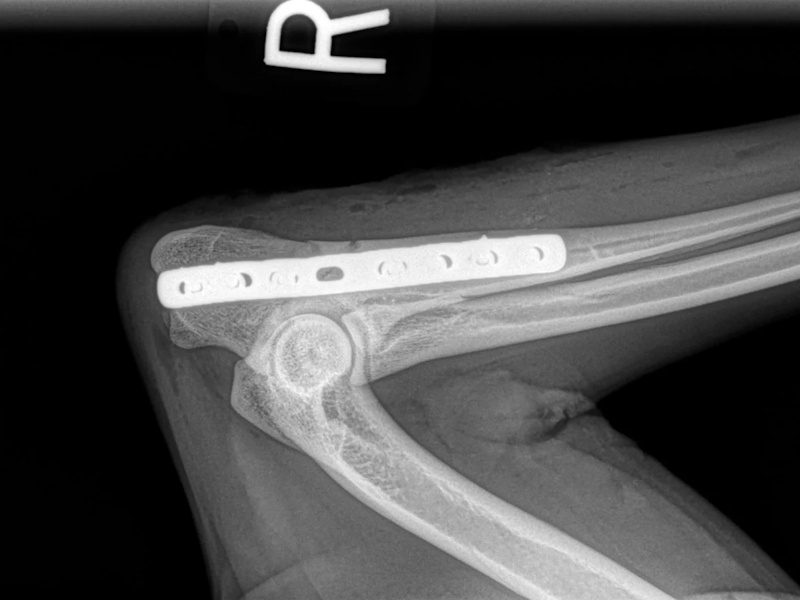

An osteotomy is a surgical cut in a bone. In the cruciate deficient stifle, a cut is made in the top of the tibia. The top portion of bone that contains the articular surface is rotated to level it. The two pieces of bone are held in place with a metal plate and screws.

Post Surgical Radiographs

While the patient is still anesthetized, the patient is taken into radiology for post-surgery radiographs (X-rays). The radiographs are assessed to measure the new tibial plateau angle. We are aiming for 5-6 degrees relative to the long axis of the tibia. The apparatus (plate and screws) are assessed for size and appropriate position.

Fore Limb (Humerus, Radius/Ulnar, Metacarpus)